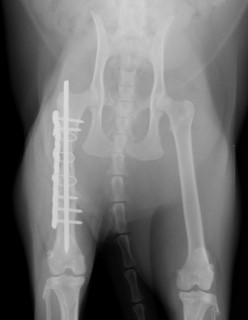

手術前 手術後

ロッキングプレートで整復しました。